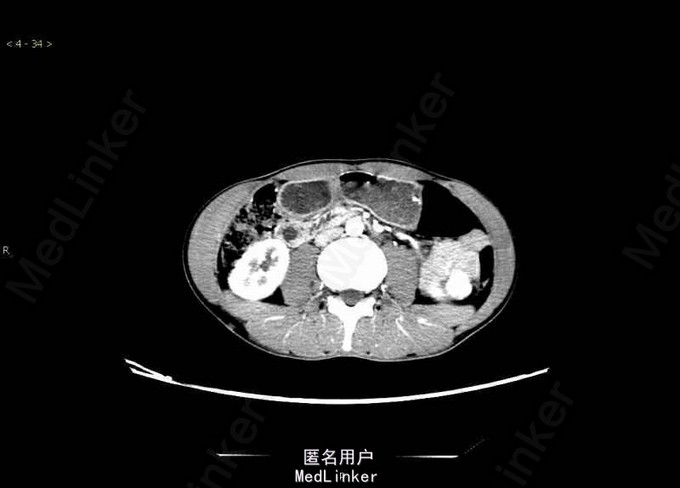

腰酸伴消瘦3月,发现左侧肾脏肿物2周。其余病史无特殊。

腰围65.5cm,臀围76cm,体型消瘦,恶液质面容。其余无特殊。 辅助检查:盆腔CT:1、左肾占位考虑肾癌可能性大。2、肝多发血管瘤。。

诊断:肾错构瘤 在全麻下行“后腹腔镜左肾部分切除术+肾周粘连松解术”,术程顺利,术后恢复好。